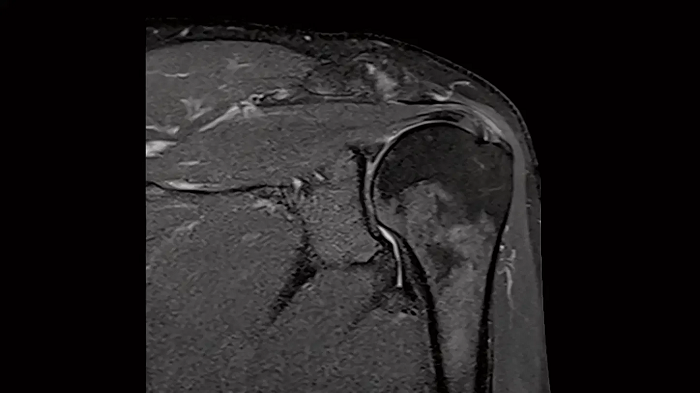

Shoulder

Shoulder - PD TSE FatSat

Exceptional fat suppression for the clear imaging of the shoulder.

Image Courtesy: University Hospital Erlangen, Germany | Image-ID: 4aaaa0384